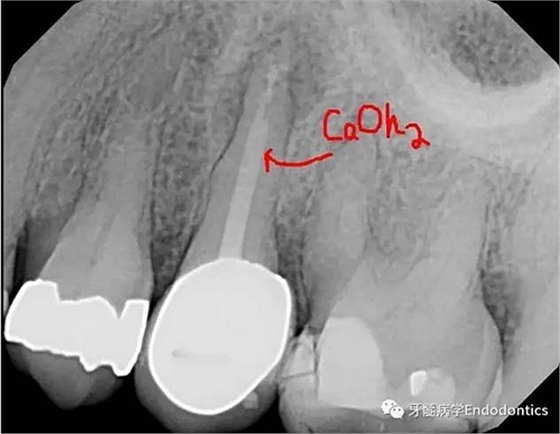

圖2.去除樁和舊充填物,氫氧化鈣封藥。